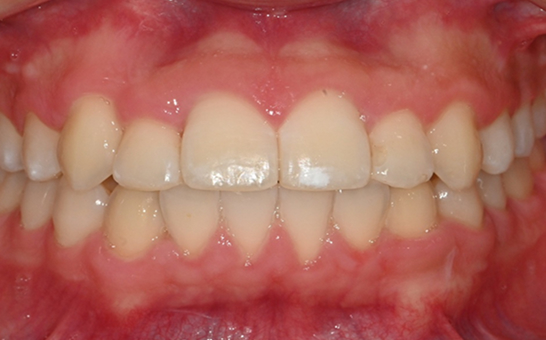

인비절라인(Invisalign)은 눈에 띄지않게 투명하게 제작된 교정 장치입니다.

치아 상태에 맞게 디지털 장비로 맞춤 설계된 투명 교정 장치를 주기적으로 교체하며 치아를 서서히 이동시키는 방식으로 진행됩니다.

기존의 금속 교정 장치와 달리 뛰어난 심미성으로

티나지 않는 교정을 원하시는 경우 적합하며 탈부착이 가능하여 위생관리가 편안합니다.

※ 바른선택치과의원은 의료법을 준수하며 위 케이스는 실제 내원 환자분의 동의하에 공개된 사진과 동일한 환자분께 같은 조건에서 촬영한 사진을 활용했습니다.

개인에 따라 진료 및 치료 방법이 다르게 적용할 수 있으며, 효과와 부작용이 개인마다 다르게 나타날 수 있는 점을 안내해 드리며, 진료 전 전문의료진과 충분한 상담을 권해드립니다.